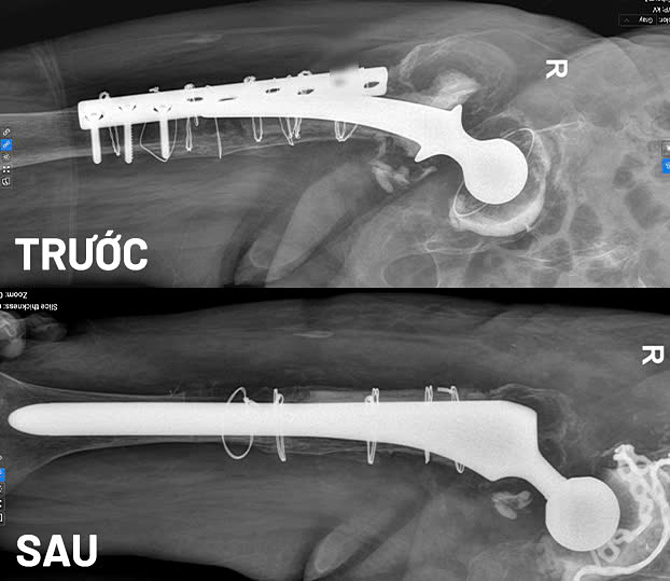

Bà An cao tuổi,thể trạng yếu,suy tim nên các bác sĩ khoa Tim mạch,Gây mê hồi sức,Chấn thương chỉnh hình hội chẩn để đưa ra phương án điều trị an toàn nhất. Chụp X-quang trước mổ cho thấy một phần đầu trên xương đùi và phía ổ cối bị tiêu xương nghiêm trọng,có vị trí gần như đứt rời,rất khó tái tạo.

Hình ảnh chụp MRI trước và sau khi bệnh nhân thay khớp háng lần thứ tư. Ảnh: Bệnh viện Đa khoa Tâm Anh